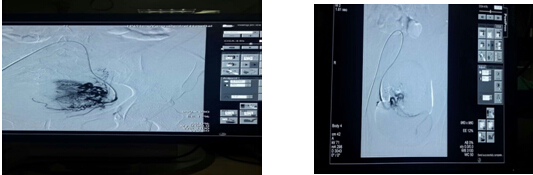

我院腫內(nèi)一區(qū)率先開展了子宮肌瘤的全新微創(chuàng)治療方法——子宮動脈栓塞術, 即經(jīng)皮股動脈穿刺,在X線造影下,通過微導管將栓塞劑置入提供子宮肌瘤的雙側(cè)子宮動脈,阻斷肌瘤的血液供應,斷其”糧草”,使肌瘤缺血缺氧而發(fā)生壞死、變性,甚至脫落、消失的一種新型治療技術。此手術顛覆了傳統(tǒng)“開刀切除肌瘤”的方式,能夠在不傷害子宮的情況下治愈肌瘤,取得良好的治療效果,深受患者的追捧,目前我科已成功為200多名子宮肌瘤患者實施微創(chuàng)手術,解除病痛。

子宮動脈栓塞前供血豐富 子宮動脈栓塞后血管堵塞

陽美玲副主任親自行子宮動脈介入術 患者康復,滿懷喜悅和感激